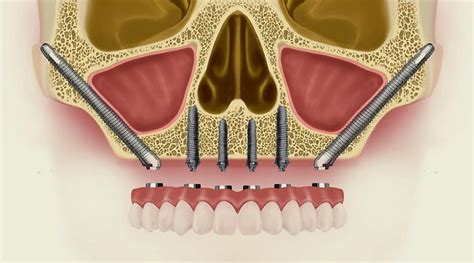

Cuando un paciente padece una pérdida o reabsorción del hueso maxilar por distintas causas, el implante cigomático permite usar una alternativa de anclaje distinta. Este tipo de implante tiene un diseño y una longitud diferente a la de un implante dental de anclaje maxilar. Siendo más largo y con un diseño especial, el implante permite al especialista anclar su estructura en el hueso cigomático o del pómulo.

El hueso cigomático es un tejido más denso y con mayor resistencia, con una mayor área cortical que el hueso maxilar, mayormente esponjoso. El procedimiento tiende a ser un poco más complejo que los implantes maxilares, pues requiere de una mayor profundización. Adicionalmente, la realiza un cirujano maxilofacial especializado. Usualmente, se hace bajo anestesia general o con una combinación de anestesia local y sedación. Los especialistas en cirugía maxilofacial de beOne realizan una serie de análisis radiológicos y de imágenes de la zona. Con ello, estudian las condiciones físicas del hueso y de toda la zona a intervenir.

El procedimiento inicia con la colocación de la anestesia que, dependiendo de la condición del paciente, puede ser local. En casos más complejos se requierá sedación o anestesia general. Luego, el dentista realiza una incisión en el hueso del pómulo, a través de la cuál tendrá acceso al hueso cigomático. Una vez hecho esto, procede a crear una osteotomía o perforación del hueso, donde se inserta el implante para fijarlo. Por último, se cierra la incisión.

Los implantes cigomáticos son un tratamiento innovador que permite ofrecer un gran número de ventajas a los pacientes con poco hueso con atrofia óseas del maxilar superior, puesto que ofrece resultados predecibles con unos resultados óptimos en cuanto a funciona y estética a la vez. La técnica en sí consiste en la colocación de los implantes en el hueso a nivel del pómulo. Este tipo de implantes son más largos de los implantes convencionales, miden entre 35 y 55 mm de largo. El hueso cigomático (pómulo) presenta unas condiciones óseas muy favorables, consiguiendo una buena estabilidad primaria del implante en todos los casos. Colocando los implantes en el hueso cigomático eliminamos la necesidad de realizar injertos óseos. Los implantes zigomáticos son un tratamiento quirúrgico que aportan seguridad, confort y estética. Así pues, devuelve a los pacientes una calidad de vida de modo inmediato. El proceso se inicia con un estudio detallado, gracias a la última tecnología en 3D.

La rehabilitación de los maxilares de los pacientes con poco hueso generalmente se realiza mediante la colocación de dos o cuatro implantes cigomáticos y de dos a cuatro implantes convencionales en la región anterior. Buen post-operatorio. Mayor tasa de éxito. Prótesis inmediata.